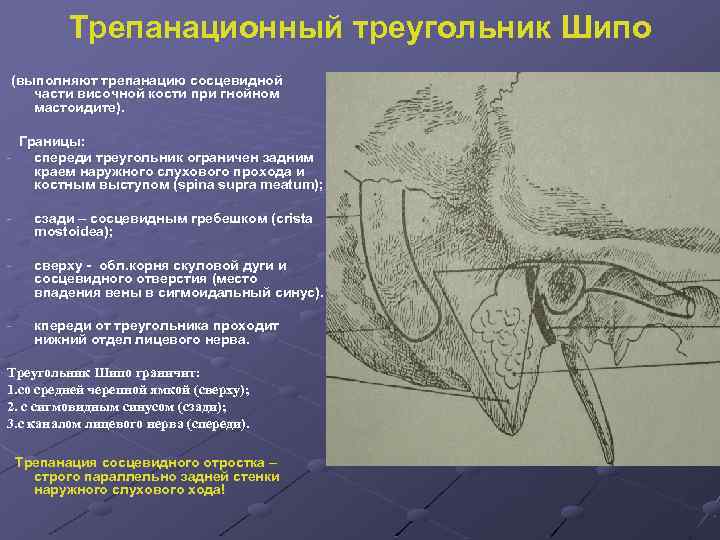

КТ анатомия сосцевидного отростка: особенности и показания